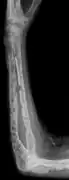

X-ray of the forearm, with lytic lesions

The diagnostic examination of a person with suspected multiple myeloma typically includes a skeletal survey. This is a series of X-rays of the skull, axial skeleton, and proximal long bones. Myeloma activity sometimes appears as "lytic lesions" (with local disappearance of normal bone due to resorption). And on the skull X-ray as "punched-out lesions" (pepper-pot skull). Lesions may also be sclerotic, which is seen as radiodense.[47] Overall, the radiodensity of myeloma is between −30 and 120 Hounsfield units (HU).[48] Magnetic resonance imaging is more sensitive than simple X-rays in the detection of lytic lesions, and may supersede a skeletal survey, especially when vertebral disease is suspected. Occasionally, a CT scan is performed to measure the size of soft-tissue plasmacytomas. Bone scans are typically not of any additional value in the workup of people with myeloma (no new bone formation; lytic lesions not well visualized on bone scan).

Bone pain affects almost 70% of people with multiple myeloma and is the most common symptom.[15] Myeloma bone pain usually involves the spine and ribs, and worsens with activity. Persistent, localized pain may indicate a pathological bone fracture. Involvement of the vertebrae may lead to spinal cord compression or kyphosis. Myeloma bone disease is due to the overexpression of receptor activator for nuclear factor κ B ligand (RANKL) by bone marrow stroma. RANKL activates osteoclasts, which resorb bone. The resultant bone lesions are lytic (cause breakdown) in nature, and are best seen in plain radiographs, which may show "punched-out" resorptive lesions (including the "raindrop" appearance of the skull on radiography). The breakdown of bone also leads to the release of calcium ions into the blood, leading to hypercalcemia and its associated symptoms.